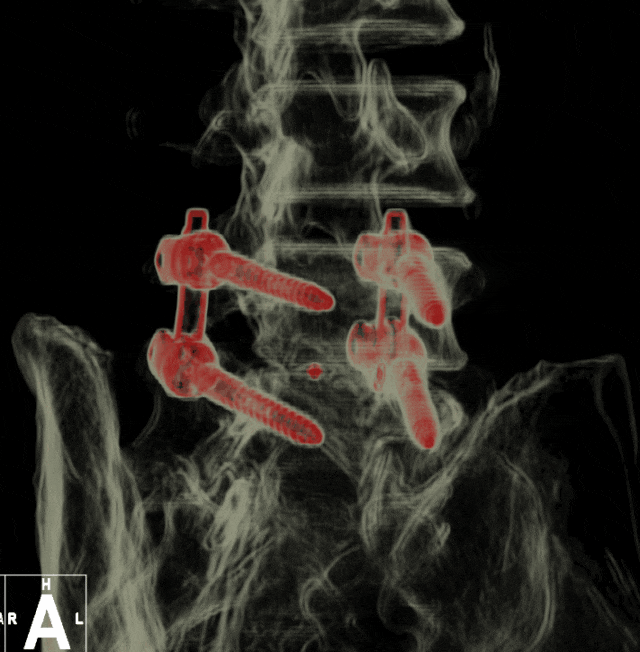

对于脊柱感染等复杂病例,3D 外视镜结合S2 AI螺钉技术。从感染控制、手术方案设计到术后康复,每一个环节都反复推敲。团队结合患者的病因差异(原发与继发)、身体状况,分别制定了个性化治疗计划,既要彻底清除感染病灶,又要最大程度保护脊柱脊髓功能,清除病灶同时重建脊柱稳定性,让患者即刻摆脱疼痛,迅速恢复正常生活。

术后复查